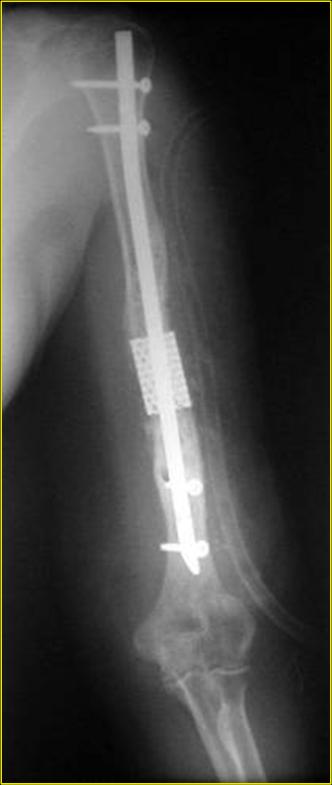

Типичная положительная ситуация для интрамедуллярного остеосинтеза с

использованием опорного металлокаркаса для компенсации дефекта.

Послеоперационное ведение активное или агрессивно-активное. Каркасы

можно заказать в МАТИ.

Рентгеновская версия реконструкции. хронология:

после операции, 2 мес. после операции, через 1 год

Движения в полном объеме восстановлены к 2 мес. после операции. Если надо могу показать мультик. Сейчас уже прошло более 3 лет, больная не

показывается. Успехов ЛАФ.